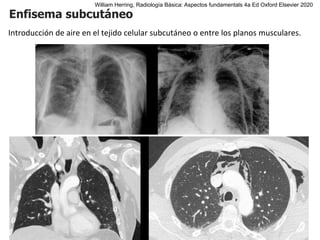

Enfisema subcutáneo

Introducción de aire en el tejido celular subcutáneo o entre los planos musculares.

William Herring, Radiología Básica: Aspectos fundamentals 4a Ed Oxford Elsevier 2020